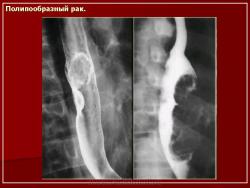

Интересные иллюстрации.

Приложения:

29m.Slayd53.JPG30m.Slayd54.JPG31m.Slayd55.JPG32m.Slayd56.JPG33m.Slayd57.JPG34m.Slayd58.JPG